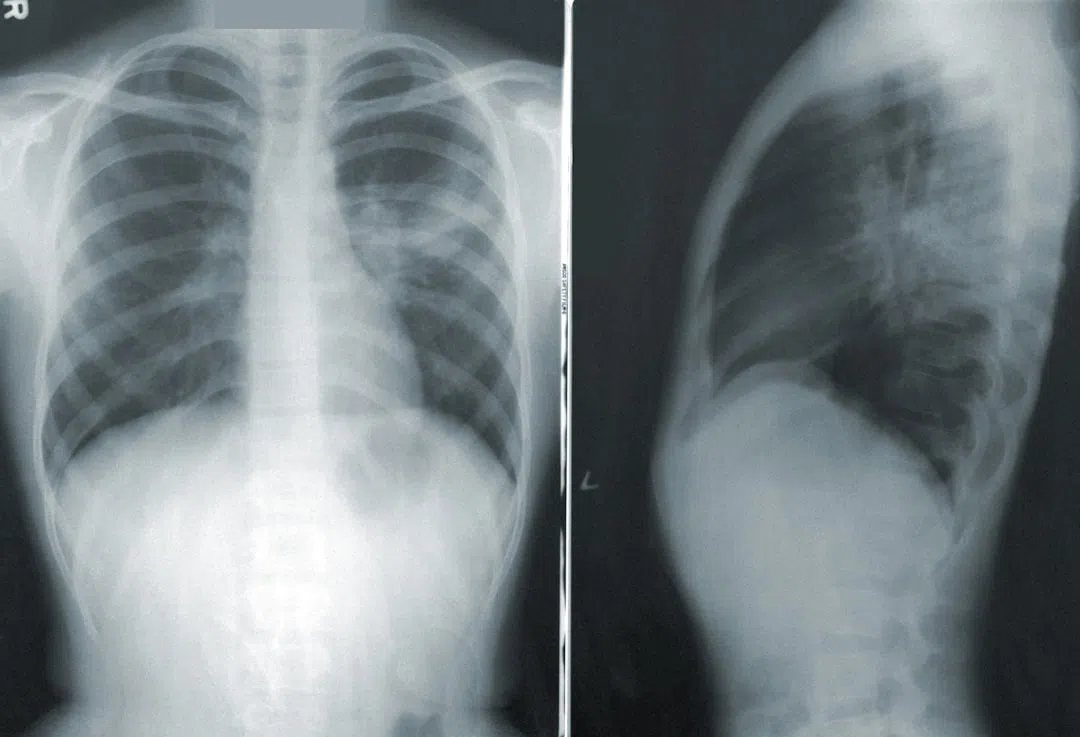

<기침과 폐통증 일반적인 증상>

기침과 폐통증의 증상이 심각하거나 지속적으로 나타날 경우에는 반드시 의료 전문가의 진단과 처방을 받는 것이 가장 중요합니다.